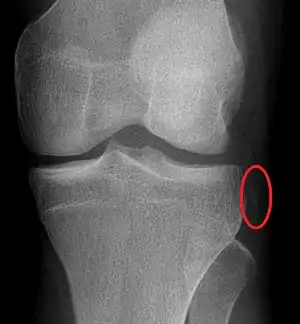

Segond fracture

The Segond fracture is a type of avulsion fracture (soft tissue structures pulling off fragments of their bony attachment) from the lateral tibial plateau of the knee, immediately below the articular surface of the tibia (see photo).

| Segond fracture of left knee | |

Segond and reverse Segond fractures are characterized by a small avulsion,[5] or "chip", fragment of characteristic size that is best seen on plain radiography in the anterior-posterior plane. The avulsed fragment of bone may be very difficult to see on the plain x-ray exam, and may be better seen on computed tomography. MRI may be useful for visualization of the associated bone marrow edema of the underlying tibial plateau on fat-saturated T2W and STIR images, as well as the associated findings of ligamentous and/or meniscal injury.